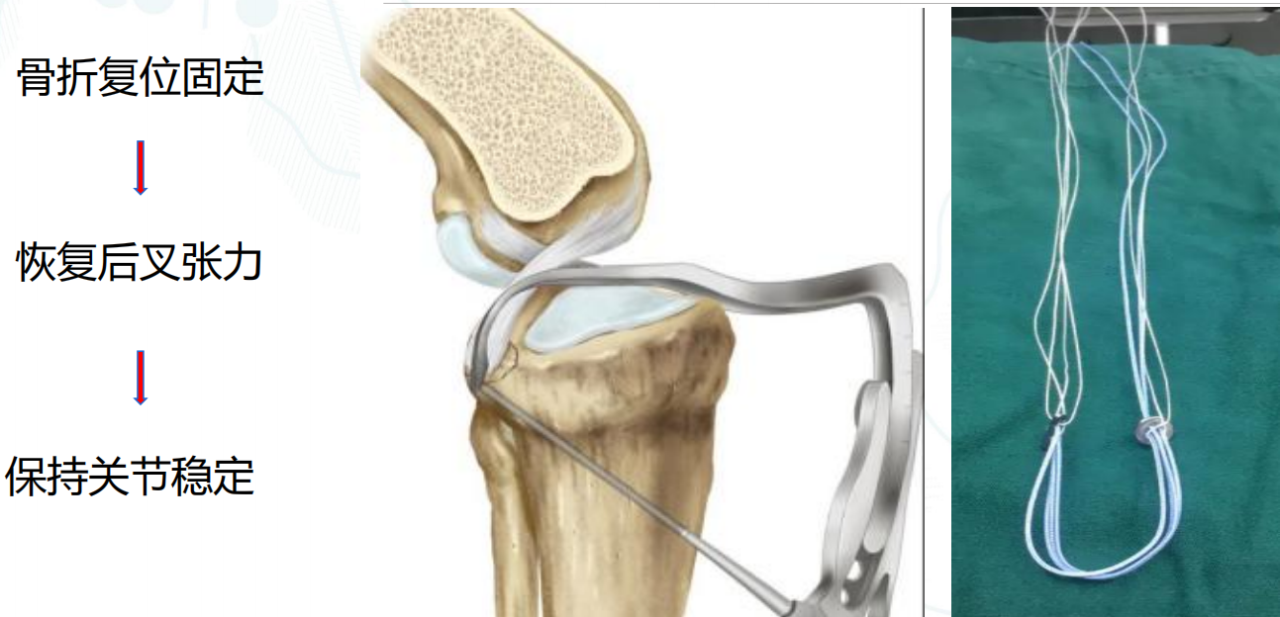

步骤1:暴露骨折段,插入定位器械,并构建一个直径为4.0mm的骨隧道。

步骤2:插入两条PDS线并引入高强线,分别并将其穿过后交叉韧带,以形成初始的吊带环。

第三步:双套环高强线复位骨折块,并穿入固定微孔钛板。

步骤4:将一根高强度缝合线穿过骨隧道,并牢牢收紧,以准确复位骨折段。

第五步:拉紧双环以稳定骨折部位,并抓住两条牵引缝线。

步骤6:紧固牵引缝线以防止固定环滑脱。

高强线+双袢+辅线防脱袢:“三重固定”;